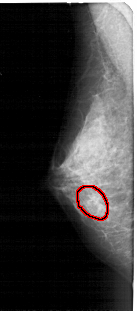

A_1475_1.LEFT_CC

LEFT_CC LINES 4246 PIXELS_PER_LINE 1921 BITS_PER_PIXEL 12 RESOLUTION 43.5 OVERLAY

FILE: A_1475_1.LEFT_MLO.OVERLAY

TOTAL_ABNORMALITIES 1

ABNORMALITY 1

LESION_TYPE CALCIFICATION TYPE AMORPHOUS DISTRIBUTION CLUSTERED

ASSESSMENT 4

SUBTLETY 3

PATHOLOGY BENIGN

TOTAL_OUTLINES 1

BOUNDARY